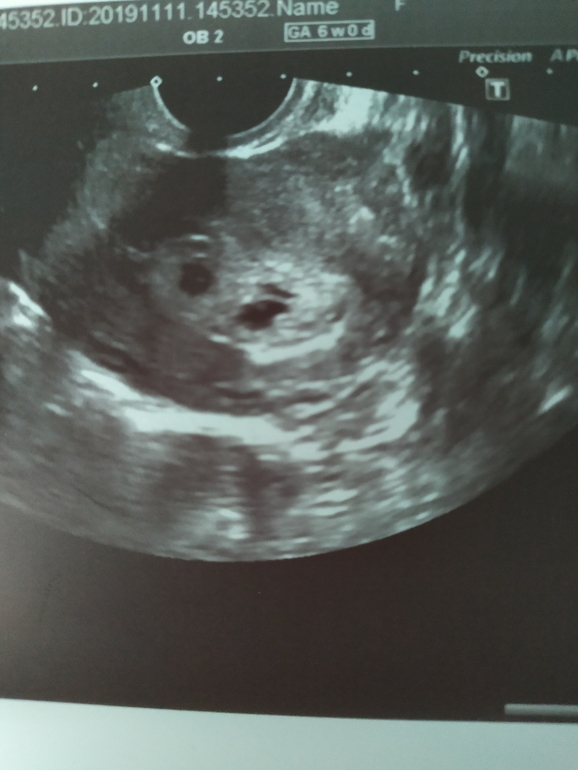

Вопросы про УЗИ, обследования и анализы: что, где, как, когда?Здраствуйте девочки! Подскажите пожалуйста сегодня сделала узи! И врач мой мне говорит: Что у меня во втором по одному яйце пусто возможно будет один малыш поставили 4-5 недель сердцебиения нет пока, жду следующую неделю. 😭😭😭😭😭😭🤰🤰🤰🤰🤰🤰🙏🙏🙏🙏🙏🙏😞Мне так страшно, хочу чтоб было всё х

Очень рано, чтобы смотреть и тем более слушать.. Но даже сейчас на снимке видно, что в обоих плодных что-то есть.. Удачи вам!

По-моему, ещё рано судить есть или нет. Насколько я понимаю, когда 2 ПЯ, то эмбрионы могут совершенно по-разному расти. То есть один дорос, чтобы увидели, а другой ещё не успел. Через недельку я думаю все уже будет видно. А вообще на снимке не пустые ПЯ, если я не ошибаюсь там видно желточные мешочки. У меня такая же ситуация была только с одним яйцом, через неделю все нашлось. Так что не переживайте раньше времени и пусть все у вас найдётся)